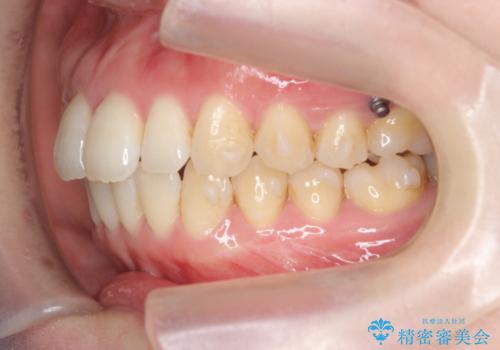

- 出っ歯に見える前歯を治したい、と矯正治療を希望され来院されました。

奥歯の噛み合わせに大きな問題はないので、目立つ前歯の角度・隙間を重点的に整え、審美的な歯並びを獲得できるよう計画します。

治療によりしっかりと前歯の角度が改善され、審美的な歯並びを手に入れることができました。